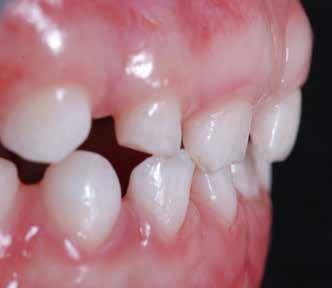

Presentazione del caso > F.V, bambino di cinque anni, presenta una malocclusione di II Classe scheletrica, III Classe dentale molare e canina destra e sinistra, morso inverso anteriore. Le arcate dentali mostrano usura degli elementi dentari anteriori a causa dell’occlusione patologica. Le linee mediane, superiore ed inferiore, sono centrate; il frenulo labiale superiore patologico per un’eccessiva estensione inter-incisale.

Il piano di trattamento prevede l’utilizzo di un dispositivo elastodontico di III Classe, da portare per due ore diurne e tutte le notti in modo passivo, senza effettuare alcun esercizio, al fine di ripristinare una relazione molare e canina bilaterale di I Classe ed il corretto avanzamento maxillare e inibire l’eccessiva crescita mandibolare. È possibile ottenere il risultato in pochissimi mesi di terapia, essendo la crescita del paziente molto attiva.

In un secondo momento, alla risoluzione della problematica scheletrica, si monitorizzerà il caso con visite semestrali in modo da reintervenire qualora si dovesse ripresentare la problematica.

Una volta ottenuta la correzione del rapporto molare ed incisale, l’apparecchio elastodontico verrà portato dal paziente solo durante la notte per stabilizzare il risultato ottenuto e guidare l’eruzione degli elementi dentari per un totale di quattordici mesi di terapia. ad inizio trattamento :

Considerazioni > L’analisi cefalometrica ad inizio trattamento dimostra la II Classe scheletrica con protrusione del mascellare superiore e prognazia mandibolare; tendenza alla crescita verticale. L’esame clinico evidenzia una protrusione mandibolare funzionale.